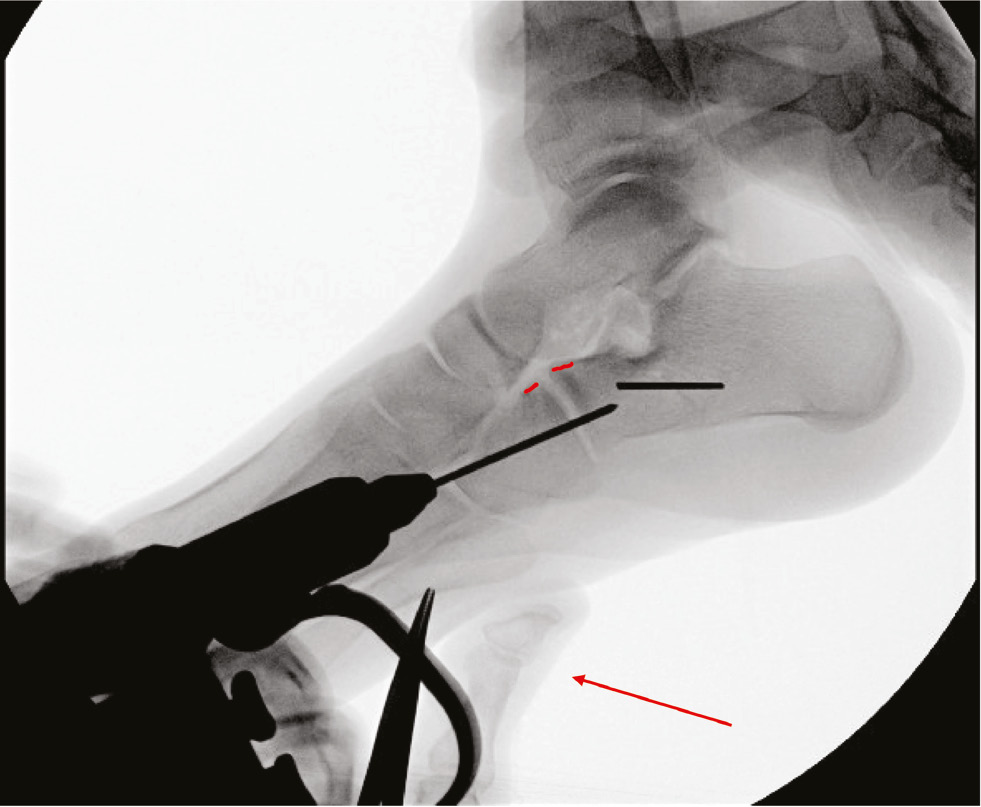

Push up on the cuboid! We wish to highlight this important intraoperative technique. It is our supposition that the reason there is no difference in rates of CC subluxation between feet that are pinned and feet that are not is because the joint is pinned with the cuboid already plantar to the distal calcaneus. If the surgeon wants to facilitate starting the pin on the dorsum of the cuboid by mildly plantarflexing the forefoot, then do so. However, before advancing across the CC joint, alter the forces and push up or dorsal on the cuboid (Figure 6). In spite of this technical modification, we still noted mild amounts of CC “subluxation” after osteotomy and graft placement, typically a 1-2 mm difference compared to standing radiographs, that are likely physiologic or rotational, but large amounts of subluxation were not seen.

Figure 6. Lateral C-arm radiograph of the foot in a 17-year-old male undergoing lateral column lengthening. Note thumb pressure (red arrow) pushing up on the plantar aspect of the cuboid as the pin is advanced across the CC joint, preserving a normal relationship of the joint (red lines).